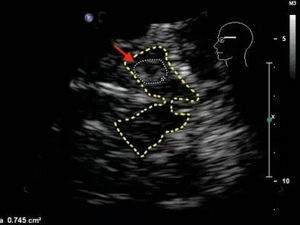

经颅彩色多普勒超声(TCCD),俗称黑质超声,德国Becker于1995年首次发现,帕金森患者的中脑黑质回声明显增强,黑质高回声是黑质纹状体多巴胺能系统存在损害的一个早期标志。

2013年欧洲神经科学协会联盟(European Federation of Neruological Societies,EFNS)制定的帕金森病诊断指南推荐:经颅彩色多普勒超声可用于:1.帕金森病的进一步明确诊断;2.帕金森病与不典型帕金森综合征和继发性帕金森综合征的鉴别诊断;3.检测帕金森病高危患者或处于运动前期的患者。